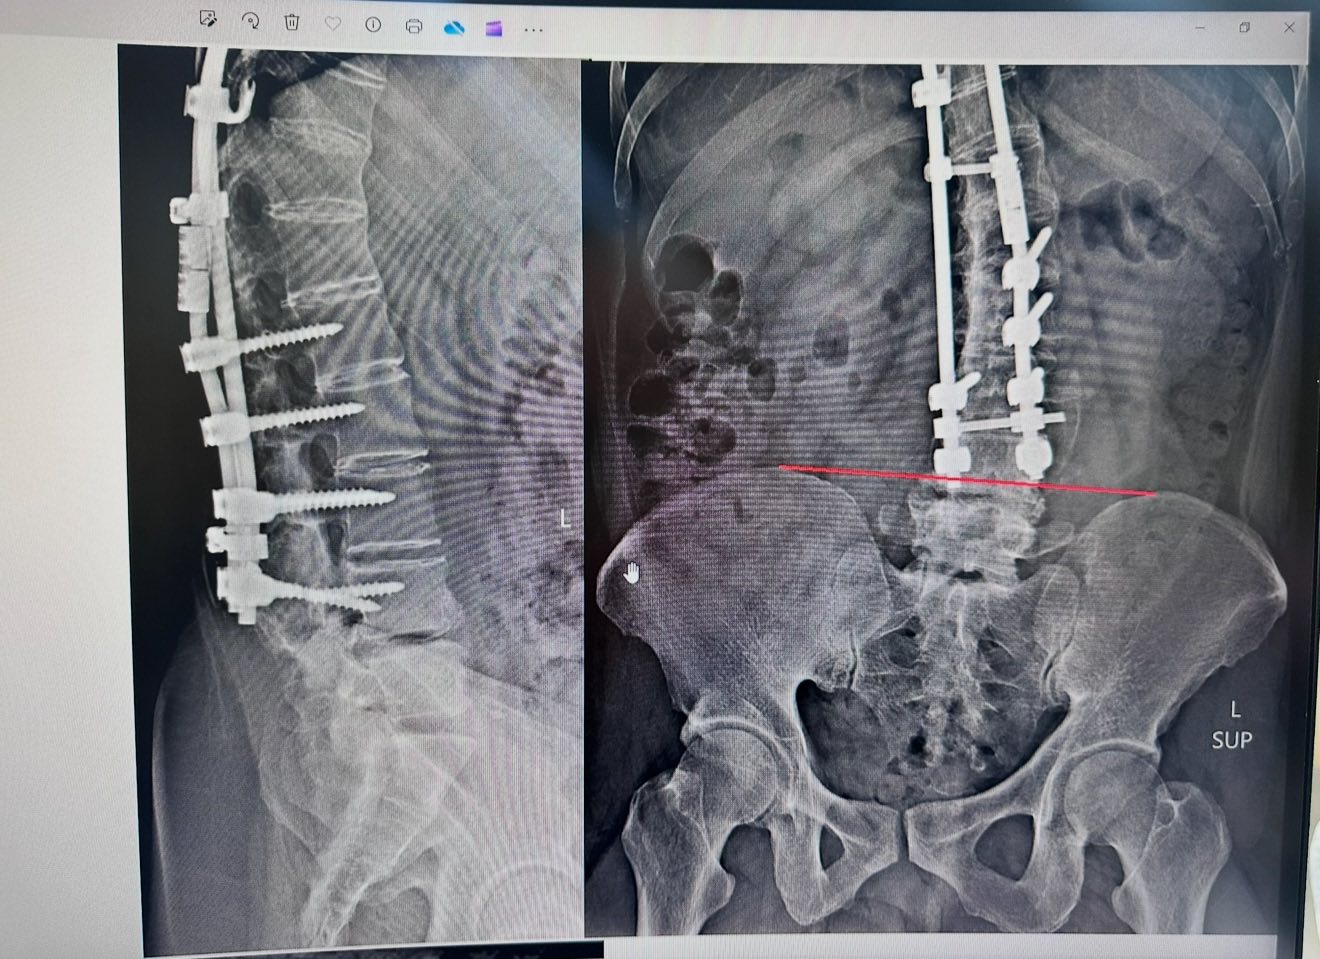

Cervical Spine Treatment Cases 腰椎治療案例 「一幅瓢瓜水墨,記錄了一段不用開刀的人生轉彎。山水之外:一位水墨大師與他的腰椎故... 2025.12.23 【醫療現場】脊椎手術後的無聲痛哭:短時間三次動刀與癱瘓的代價——當手術刀無法解決... 2025.11.25 醫師的沉思:當長輩開始走路越走越彎 腰椎滑脫與狹窄的四大症狀警訊一定要看懂 【文... 2025.11.18 你的背痛,真的是一場「世紀大騙局」嗎? —— MRI是共犯?醫師被蒙蔽?椎間盤根本是... 2025.10.30 🌿特殊醫案|她以為是椎間盤突出或足底筋膜炎,但其實是Vit B6服用過量中毒 ⁉️維他命... 2025.10.22 椎間盤突出逆轉勝:從「破裂」到「復原」的醫學證據。 一位針刀醫師的真實告白。 椎... 2025.10.20 為什麼神經傳導檢查這麼重要? 為什麼說黃金治療期就是100天內? 為什麼核磁共振影像... 2025.10.20 醫案故事:高球名將Tiger Woods 的第七刀 ——當傳奇背後,是一條被切七次的脊椎 老... 2025.10.16 美國開腰椎手術要兩百萬?VS 台灣三週針刀療程的奇蹟 2025.09.23 五年之內歷經三次脊椎大刀之後的醫療反思。 下背手術失敗綜合症候群的一些觀點 脊椎微... 2025.09.22 「脊椎手術有它的價值,但不是每個人都需要大刀──針刀療法給病人多一個選擇」 📌 脊... 2025.09.18 #巨大椎間盤突出一定要開刀嗎? #三家醫院骨科醫師說很嚴重需要手術 #難道真的沒有第... 2025.09.17 ⭕️巨大椎間盤突出,PRP治療失敗、痛到掰咖…他差點走上手術台,卻在這裡看見奇蹟 ⭕️醫... 2025.09.07 【少棒奪冠、脊椎隱憂與台灣棒球的困境】🇹🇼⚾️ 「睽違29 年後的淚水,背後卻有個殘酷... 2025.08.25 ✈️【一張差點被腰痛奪走的法國機票】 ✅一張飛往法國的機票,因為「腰椎管狹窄」而延宕... 2025.08.21 1 2 3 4 5 下一頁 →